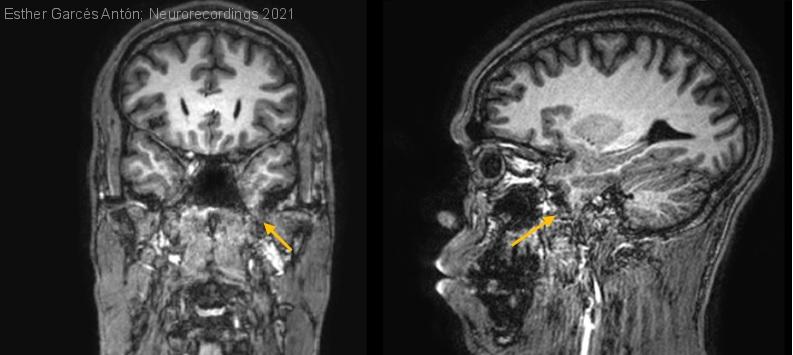

Diagnóstico final: Encefalocele temporal izquierdo

Varón de 42 años, diestro, con historia de 5 años de epilepsia farmacorresistente sin lesión en neuroimagen. Antecedentes: parto sin complicaciones, desarrollo psicomotor normal, no crisis febriles, no infecciones ni traumatismos del SNC. No antecedentes familiares...